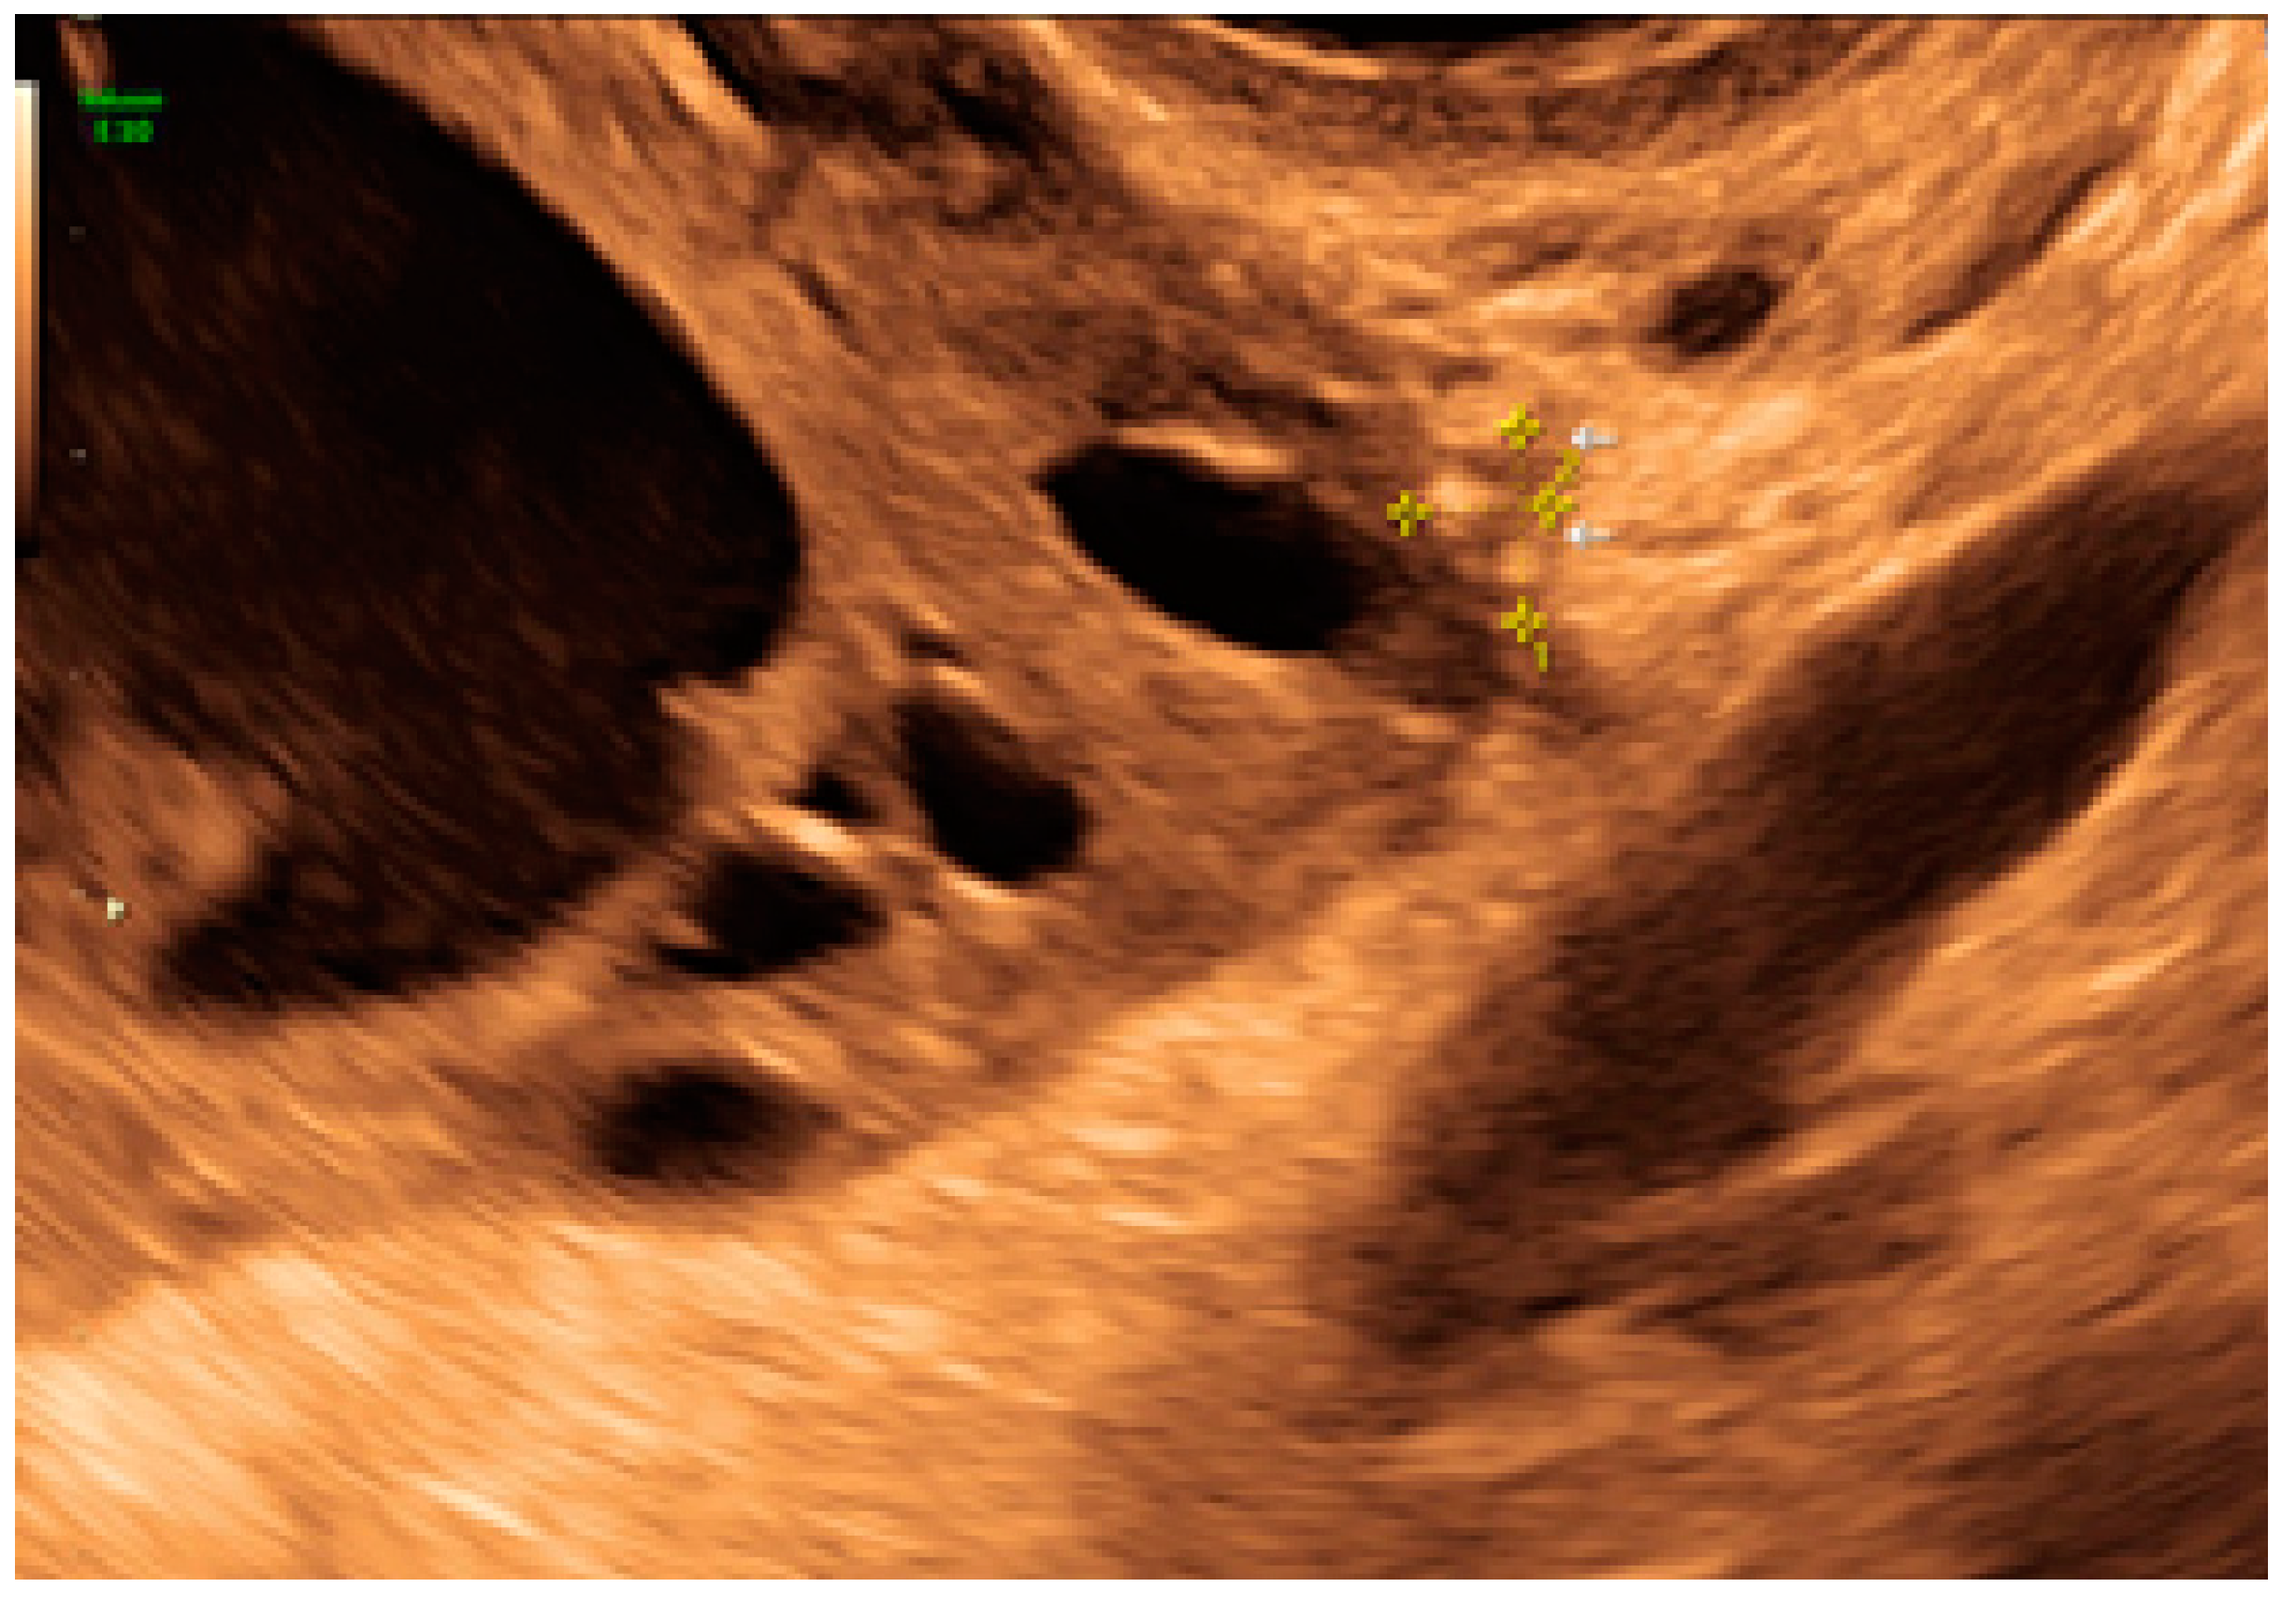

- The presence of hyperechoic foci (we called this a “pearl”).